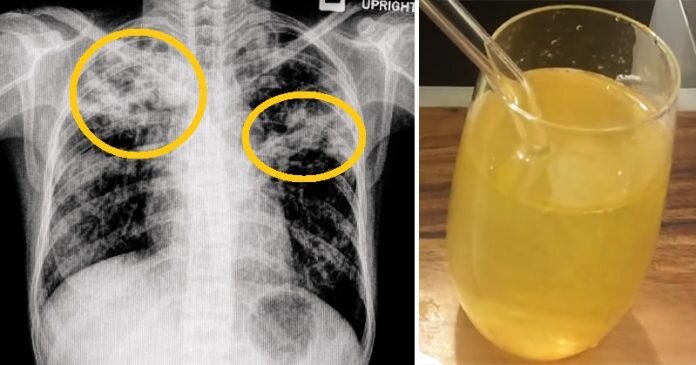

Все чувствуют себя ужасно, когда слизь и мокрота накапливается в носовых проходах или в горле. Это дополнительно вызывает герметичность в грудной клетке, постоянный кашель и проблемы с дыханием.

Следующие 5 природных средств быстро устраняют слизь и мокроту:

Яблочный уксус — невероятно полезное природное чудо, которое регулирует баланс pH в организме и предотвращает чрезмерное продуцирование слизи.

Вы должны добавить чайную ложку сырого, нефильтрованного яблочного уксуса в стакан воды, перемешать и выпить его несколько раз в день, чтобы удалить мокроту. Чтобы успокоить больное горло, вы также можете полоскать горло этим средством.